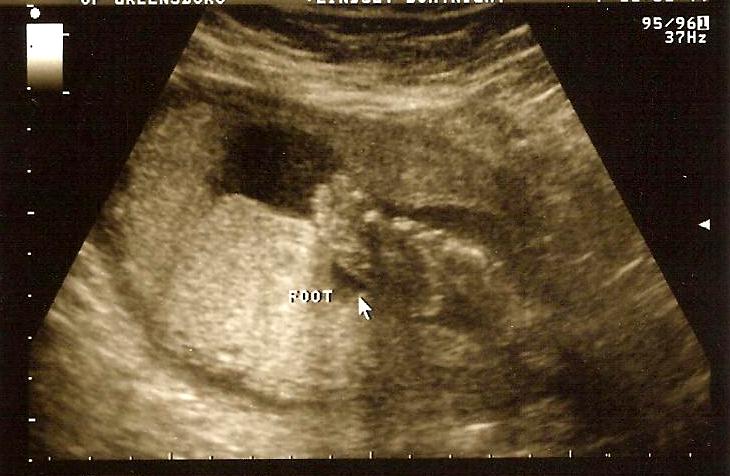

we went in on friday to check the progress of the previa and also to get some additional pictures of Audrey's heart that they were not able to get last time because she was so sleepy and bunched up in a weird position. this time though, we had the opposite problem -- girl would not stop moving! there were arms and legs flying around everywhere! she was really active all the way to the appointment and even more so during the ultrasound. at one point in time she had her foot above her head! it was so surreal to FEEL her kicking me and SEE it at the same time. i was laughing and crying all at once -- she has such a personality already and i am so proud of her! we also saw her blinking, opening and closing her mouth, and wiggling her butt around making it almost impossible for the tech to even get a measurement in! everything looks perfect and she now weighs a whopping 1 lb. 5 oz.

| what it looks like in there when i feel her kicking me :) |

| teeny tiny feet! one foot is flat and one is laying across the other |